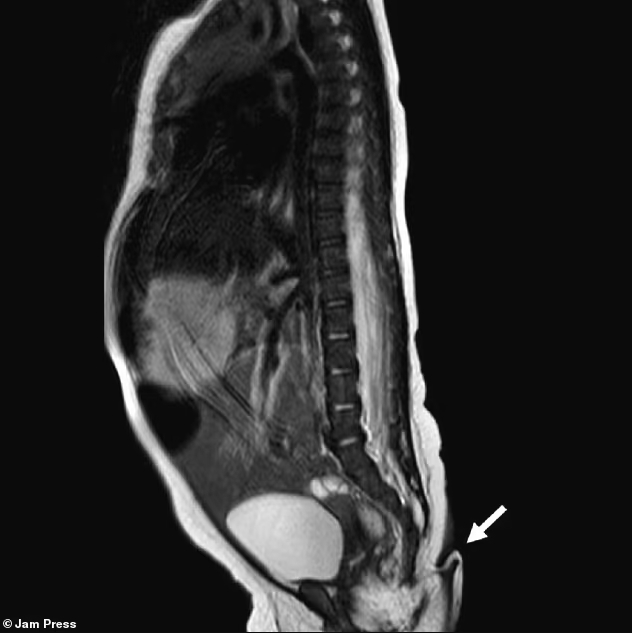

Однако при осмотре врачи обнаружили у нее хвост - в 5,7 см. Он был мягким, с заостренным кончиком, покрыт кожей и тонкими волосками.

Дотронуться до хвоста и даже его немного покрутить было можно - боли это не вызывало. Но самостоятельно хвост не двигался. Девочке сразу провели тест на реакцию - при легком уколе отростка малышка заплакала.

Новорожденной провели полное медицинское обследование и никаких отклонений не обнаружили - она была абсолютно здорова. Сканирование показало, что хвост не был результатом проблем с позвоночником.

Ранее были известны случаи спинальной дизрафии, при котором происходит неправильное формирование позвоночника и возможно появление хвостовидного отростка в нижней части.

Первые несколько месяцев врачи наблюдали за отростком и обнаружили, что хвост растет вместе со своей владелицей. За два месяца отросток увеличился на 0,8 см.

Ученые отмечают, что подобные отростки делятся на два типа - псевдохвосты, которые выглядят как хвосты, но возникают из-за проблем с позвоночником или опухолями.

А есть и настоящие хвосты, которые содержат мышцы, кровеносные сосуды и нервы. В таких хвостах нет костей. Именно такой хвост и был у малышки из Мексики.